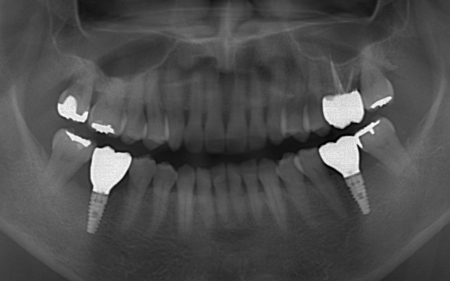

| カウンセリング | 拝見したところ、上下左右の奥歯計8本(第1大臼歯、第2大臼歯)に重度の歯周病が認められました。 歯周病は歯を支えている骨や歯ぐきに炎症が起こる病気です。進行すると歯がぐらついたり、噛む力が弱くなったりします。 さらに悪化すると歯を失う可能性が高くなるだけでなく、周囲の歯にも影響が広がることがあります。 特に下の奥歯2本(左右第1大臼歯)は歯を支えている骨が著しく減少して歯が大きく揺れており、治療して温存することは難しい状態でした。 また、左上の奥歯(第1大臼歯)は過去に詰め物で治療されていましたが、その下で虫歯が再発しています。 以上のことから、下左右の第1大臼歯は抜歯後に歯を補う治療、その他奥歯の治療、再発した虫歯の治療が必要と診断しました。 |

診断結果を踏まえ、まず下左右の第1大臼歯については抜歯したあとにインプラントで補う方法を提案しました。

インプラント治療は、周囲の歯を削ることなく失った歯の部分のみを単独で補うことができます。 ただし、外科手術が必要となり治療期間が比較的長くなる点がデメリットです。 次に歯周病が認められるその他の奥歯については、歯周組織再生療法を行いできるだけ歯を抜かずに残す方法を提案しました。

さらに虫歯が再発していた左上奥歯については、虫歯をしっかりと取り除いたうえで被せ物による修復治療を提案しました。 それぞれのメリット・デメリットを丁寧に説明したところ、治療計画に同意いただきました。 まず、歯周基本治療から開始しました。 下左右の第1大臼歯を抜歯し、その部位にインプラントを埋め込む手術を行いました。同時に、インプラントの隣にある下の第2大臼歯に対して歯周組織再生療法を施しています。 また、左上の奥歯は虫歯を取り除いたあと、歯の形を整えて型取りを行い、最終的にジルコニアクラウンを装着しています。 段階的に治療を進め、すべての治療を終了しました。 |